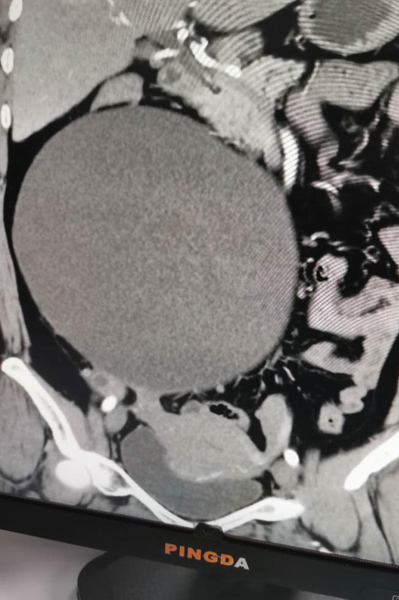

近半月腹部悶脹感加重,仰臥不能,伴頭暈、頭痛、四肢乏力,心悸胸悶、納差食少,當(dāng)?shù)乜h人民醫(yī)院檢查發(fā)現(xiàn)盆腹腔有一巨大包塊性質(zhì)不詳,進(jìn)一步CT檢查示:右側(cè)腹腔巨大包塊影(20x18cm),診斷為:1、盆腹腔巨大包塊性質(zhì)待查;2、高血壓3級(jí)極高危組;3、高血壓性心臟病;4、混合型高脂血癥;5、子宮肌瘤等多病。因患者盆腹腔包塊較大,合并基礎(chǔ)疾病較多,建議到上級(jí)醫(yī)院行手術(shù)治療、明確性質(zhì),遂于2020年10月19日就診于我院并收住婦科。

經(jīng)充分術(shù)前準(zhǔn)備后于10月23日在全麻下由婦科聯(lián)合外科團(tuán)隊(duì)緊密配合下成功開展盆腔巨大包塊切除+子宮肌瘤剝除術(shù),術(shù)中切除來源于右側(cè)附件(卵巢)巨大包塊約21x19x13cm,子宮前壁肌壁間肌瘤約4x3cm。術(shù)后配合中醫(yī)藥調(diào)理,患者腹脹、頭暈、頭痛、四肢乏力等不適癥狀消失,順利康復(fù)于2020年11月01日平安出院。